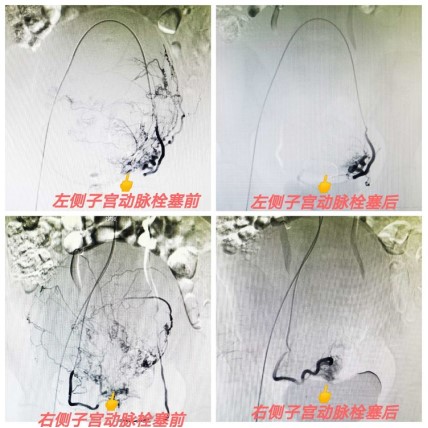

良、惡性腫瘤介入治療